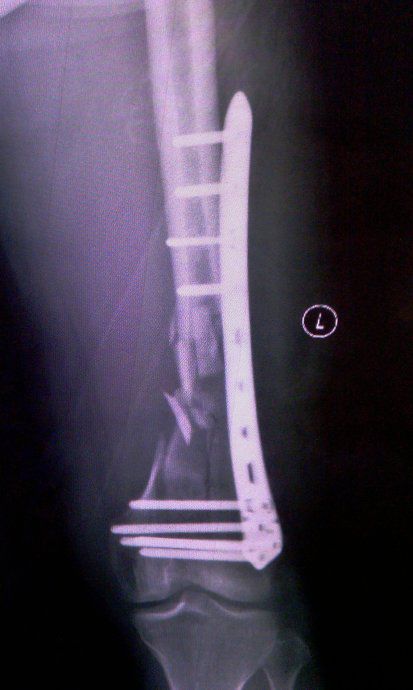

这是一种中和钢板的改版,针对于干部的粉碎骨折,通过透视下监视,使得钢板跨越骨折区域而固定骨折的近端和远端,骨折区域不进行固定。

该类技术主要是强调对位、对线、长度、旋转,中间粉碎可以不用处理,有效保护骨折断端血运,但是需要注意钢板需要有足够的长度,两端固定也需要有足够的螺钉数量。目前容易出现一些骨不连的现象,需要谨慎对待。